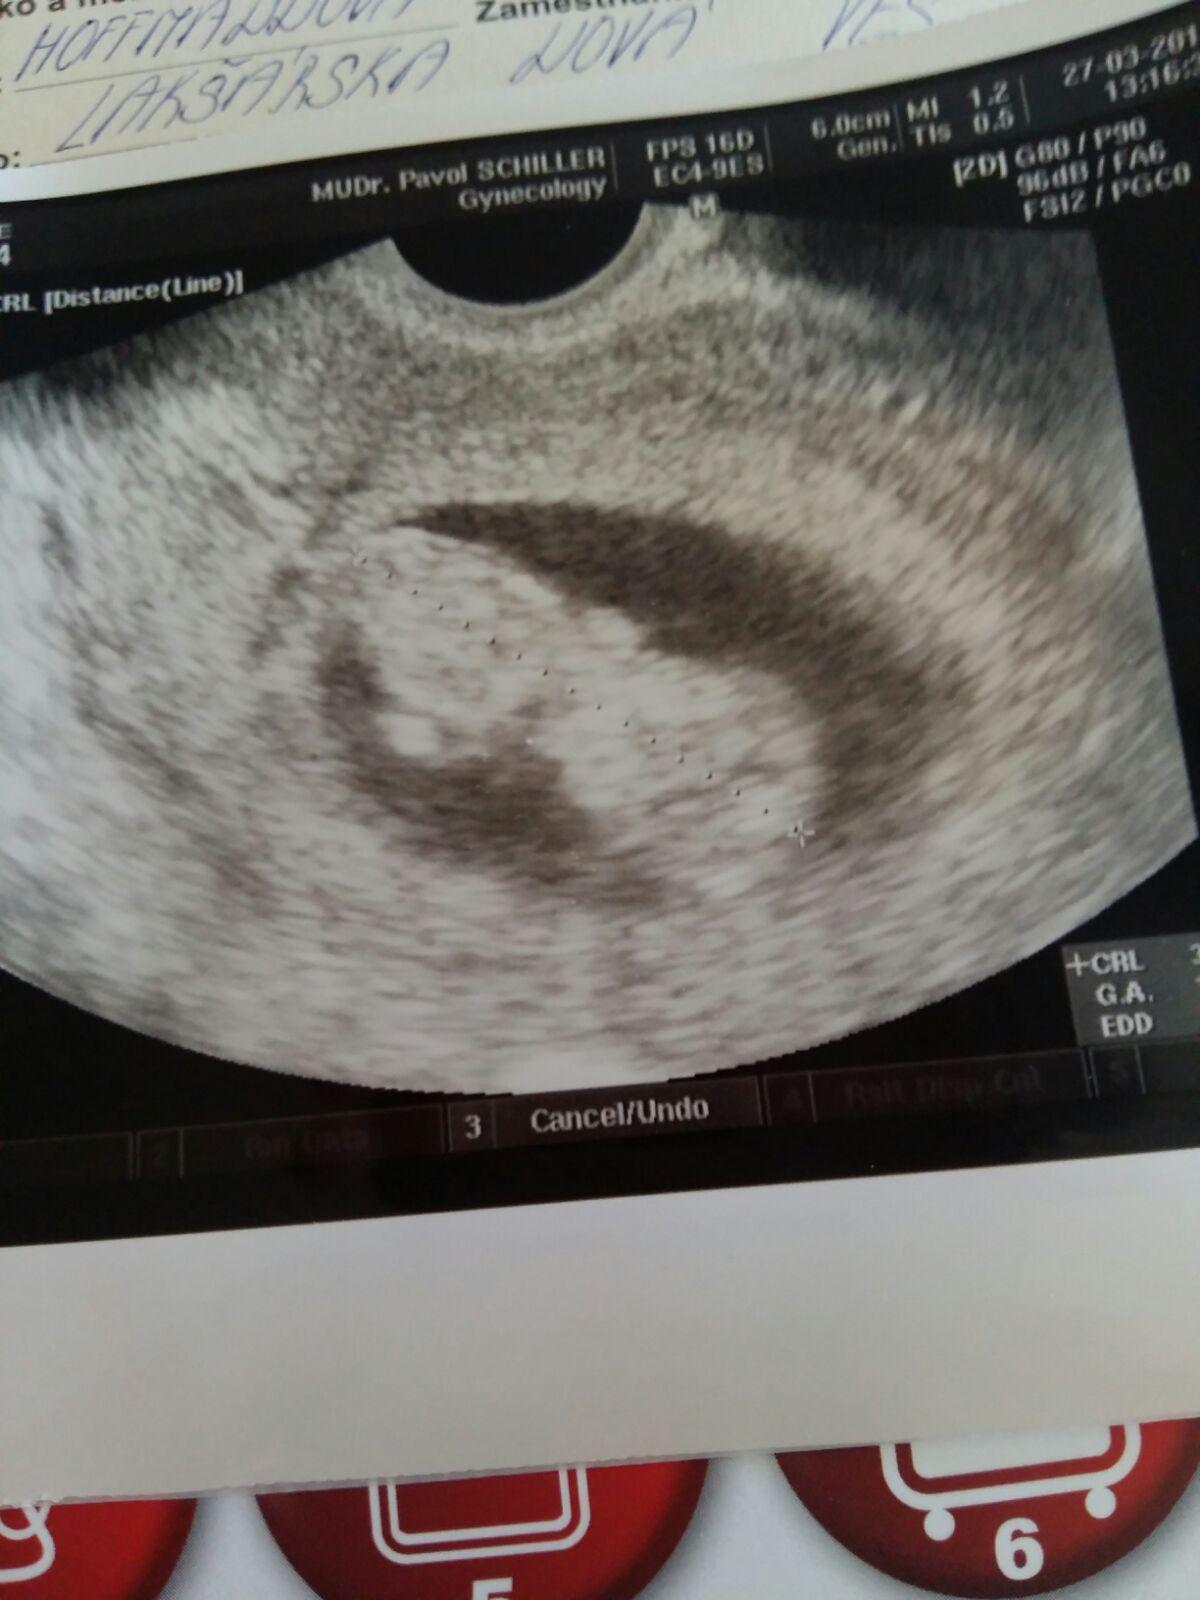

@butterfly333 pri takomto hcg by to na sone aj tak nevideli..ale nema vyznam to nadalej natahovat..pri normalnom tehu by som za takych okolnosti uz mala mat hcg niekolko tisic..nie toto..proste sa to musi umelo prerusit..som z toho smutna..ale nechcem sa poddat-.